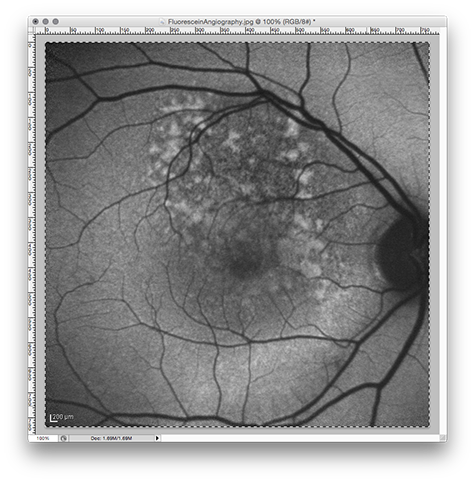

Fluorescein angiography is a technique for examining the circulation of the retina and choroid using a fluorescent dye and a specialized camera. In the fluorescein angiography image a choroidal melanoma typically shows a mottled hyperflourescence and diffuse late staining of the mass and its overlying subretinal fluid.

Fusing a fluorescein angiography image with the retinal collage can at times help to locate the fovea and to differentiate tumor from other forms of retinal damage that give an abnormal appearance to portions of the retina.

Rescale FluoresceinAngiography.jpg

The file FluoresceinAngiography.jpg is already a good size for Plaque Simulator at 768x768 pixels. All we need to do is change the original dpi from 96 to 72. In the Image Size window, change the pixel dimensions and document size popup menus from pixels to percent. The width and height fields will change to read 100%.

Then change the document size resolution from 100 to 72 pixels/inch. Click the OK button to close the Image Size window.

PhotoshopFAOriginal